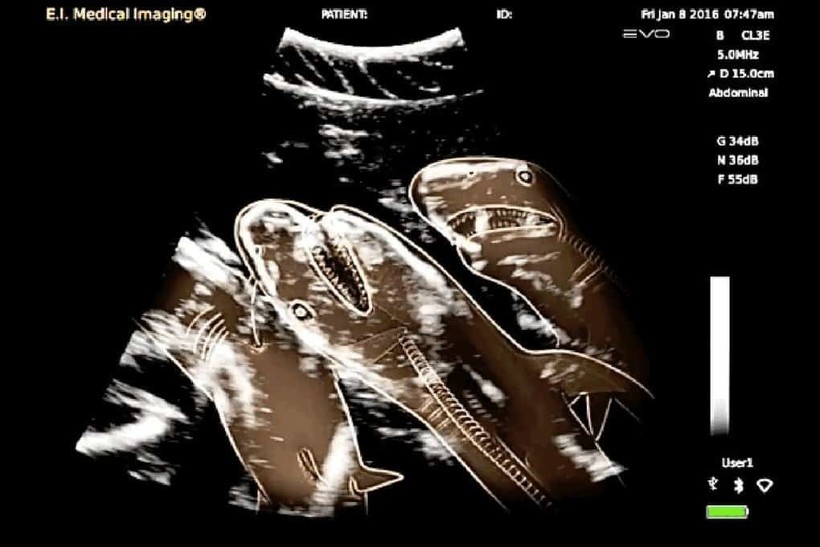

УЗИ акулы